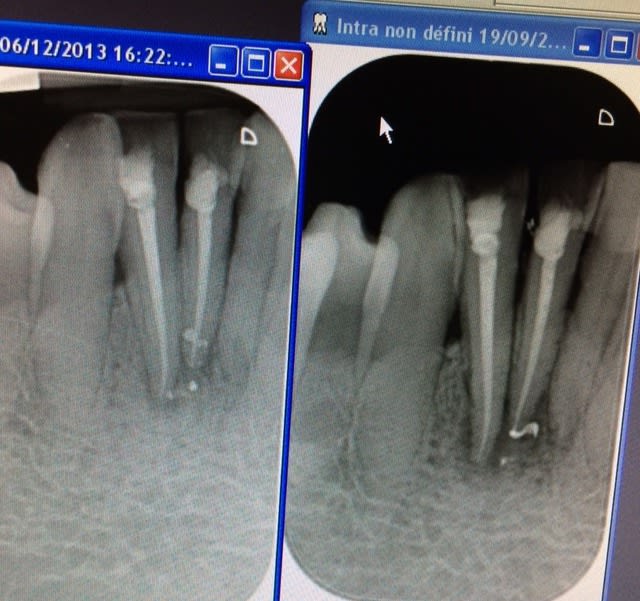

Voila un des rares cas de grosse lésion que j'ai operé cette année.

Aucune evolution en quasiment 1 an de cicatrisation

Quand j'ai ouvert il s'agissait bien d'un kyste avec un revêtement qui couvrait la totalité de la cavité (couleur nacré au fond de la cavité).

Le truc marrant dans l'histoire c'est que je n'ai pas fait de résection apicale car l'os s’était reformé autour des apex grâce a mon endo.

Le kyste evoluait pour son propre compte (principe du kyste).

Voila pourquoi il faut toujours attendre avant d'operer.

Pour ceux qui ont remarqué a juste titre la parodontite severe avec le tartre je precise qu'il s'agit d'un patient à la comprehension limite et que le traitement global s'approche plus du palliatif que du curatif.